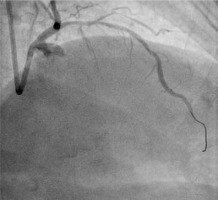

Dissection after predilatation, before BVS implantation, occurred in 22 patients, and in 17 of them it was covered by BVS implantation with optimal angiographic results. Five of them were finally in the dissection group. In another 4 patients from the dissection group, dissection appeared after BVS implantation and required additional intervention, but it was absent after predilatation. The description of dissection according to the NHLBI classification [2] is presented in Table I. Examples of angiographic images of individual dissection classes are shown in Table II.

Table II

Coronary artery dissection – classification